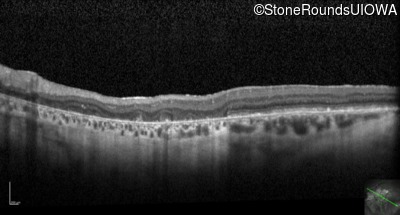

Optical Coherence Tomography - Right - 20/80

Exemplar / OCT Stack

OCT Stack

Optical Coherence Tomography - Left - 20/400